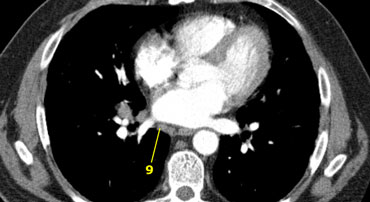

9. Hạch trong dây chằng phổi (Pulmonary Ligament)

Nodes lying within the pulmonary ligaments.

9. Trong dây chằng phổi

9. Hạch ở dây chằng phổi

Nằm ở dây chằng phổi, bao gồm thành sau và phần dưới của tĩnh mạch phổi dưới.

9. Pulmonary Ligament: nodes lying within the pulmonary ligament.